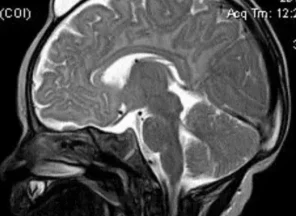

Иссечение дермальных синусов, дермоидных кист и перикраниальных синусовРазличают краниальный и спинальный дермальный синусы. Дермальный синус может заканчиваться как в мягких тканях, так и проникать в полость черепа или позвоночного канала. В последних случаях имеется высокий риск развития менингита. Лечение только хирургическое, проводится полное иссечение синуса. При распространении синуса до твердой мозговой оболочки свищ иссекается вместе с окружающим участком твердой мозговой оболочки. Дефект твердой мозговой оболочки герметично ушивается.